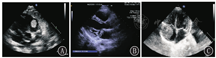

本组21例中,13例患儿行心脏肿瘤的完全切除或部分切除术[横纹肌瘤(图1A、图2A、图3A)4例、黏液瘤(图1B、图2B、图3B)3例、纤维瘤3例、炎性肌纤维母细胞瘤(IMT)(图1C、图2C、图3C)2例、畸胎瘤1例],围术期无死亡。术后随访3个月~7年,3例再次复发,其中2例黏液瘤患儿分别于术后1、3年出现肿瘤复发,均行二次手术切除治疗,术后随访5个月~1年无复发;1例IMT患儿,术中探查肿瘤浸润右心房及冠状动脉壁,行肿瘤部分切除术,术后予克拉霉素抗炎治疗2个月,术后1周残余肿瘤迅速增大,术后1个月肿瘤大小趋于稳定,术后10个月复查肿瘤消失。